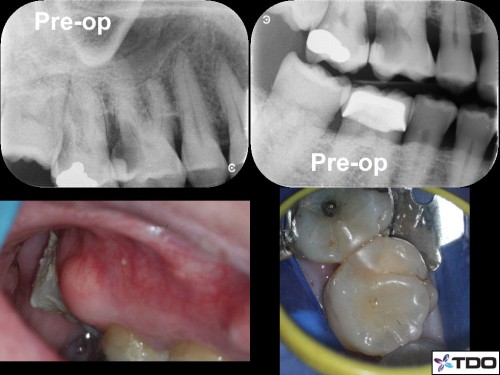

Restoring with Amalgam. 72yom. The patient had avoided the dentist due to dental anxiety. Tooth #3(16) SIP and #2(17) responded normally to all clinical tests. I recommended attempting to save both molars but he hesitantly agreed to start with tooth #3. Image Guided Treatment using CBCT aided in confirming the presence and location of MB2. The Opaldam matrix, first described by Dr. Michael Trudeau, is useful when using amalgam to restore teeth with deep interproximal caries especially when one or more corners are lost. In the end, the patient elected to extract the second and third molars and the amalgam restoration was incorporated into a Deep Margin Elevation for crown placement.